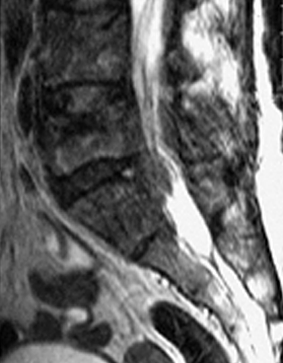

The magnetic resonance cans performed before and after the treatment are defined by a radiologist friend who is a hospital department head as “shocking” in their difference.

Before the treatment, August 25, 2000.

RMN dated August 25, 2000. In image 8a the metastatization of the 4th and 5th lumbar vertebrae and the mass that obstructs the medullar channel can be seen. Please note the tumoral mass that has invaded the marrow of the sacral part as well.

August 25, 2000 – Before treatment